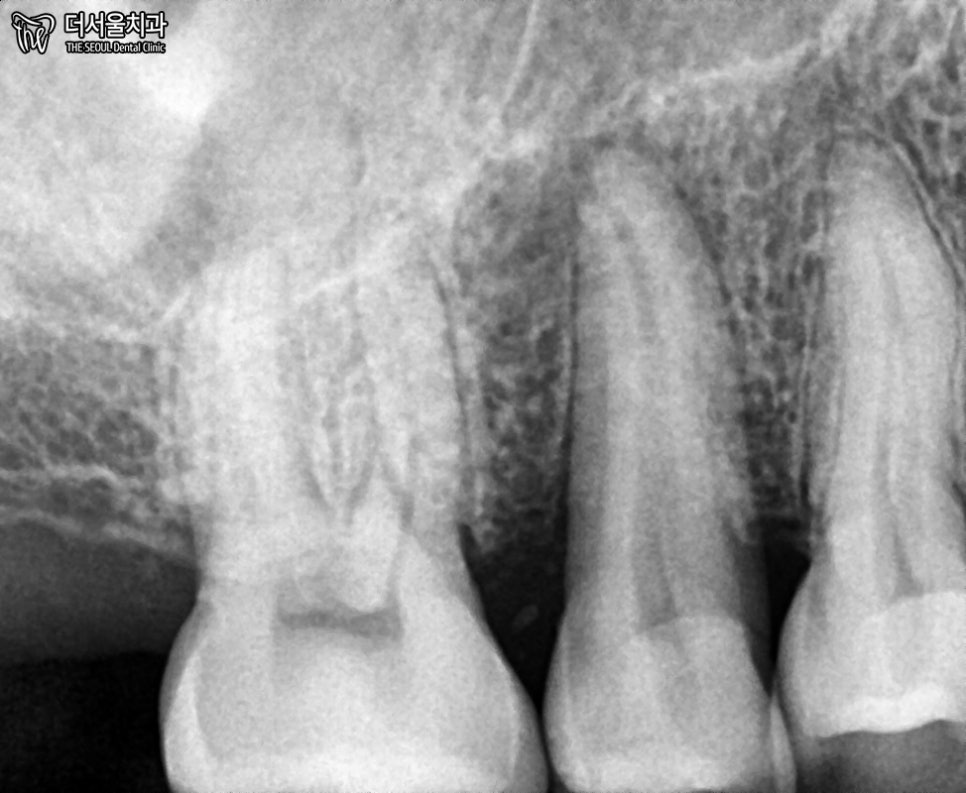

엑스레이로는 확인이 어렵습니다.

아마 수직으로 깨졌을 텐데요.

3D CT를 통해 확실히 체크해보겠습니다.

해당 치아입니다.

오른쪽에 단면을 보면,

수직으로 깊게 깨져있죠?

뿌리까지 파절되었기에

이를 살릴 수 없었습니다.

어떤 방향으로 봐도

뿌리까지 깊게 그어져있는 선을 볼 수 있습니다.